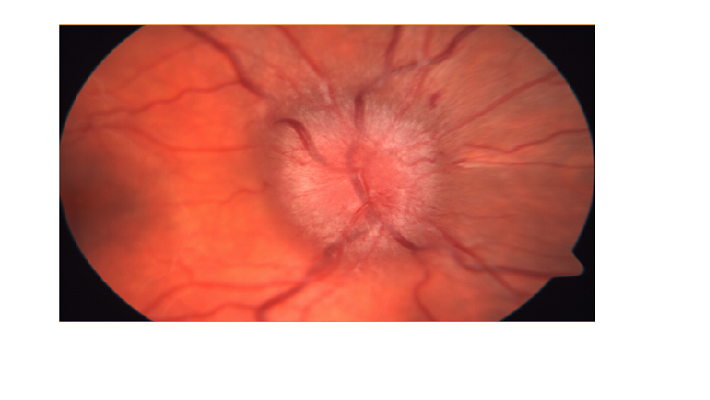

יתר הלחץ התוך גולגולתי יגרום להרמה ובצקת של ראש עצב הראייה הנכנס לעין. בצקת זו נגרמת כיוון שעצב הראייה הוא המשכי למוח ועטוף בקרומים ובנוזל המוחיים ולכן עליה בלחץ ועודף הנוזל יערבו את עצב הראייה.

במקרים בהם יש חשד לעלית לחץ בראש, רופא העיניים יכול לאבחן את הבצקת בעצבי הראייה הנקראת פפילאדמה (PAPILLEDEMA).

בתמונה: בצקת בעצב הראייה הנגרמת בשל לחץ תוך גולגלתי מוגבר